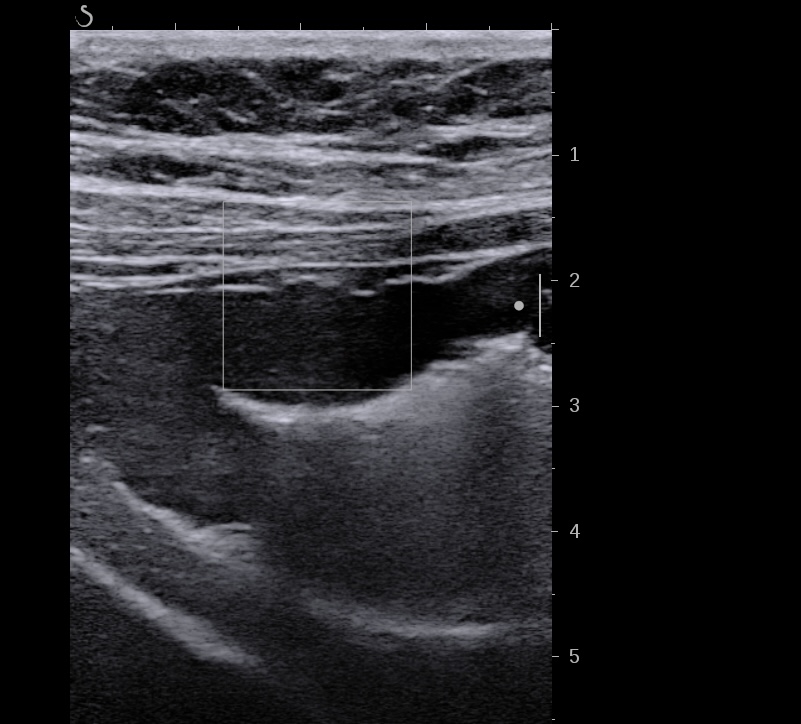

Nouvelle échographie à J15, La paroi est moins épaisse mais la structure en couche n’est pas totalement réapparue, le score de Milan MUC est alors à 6,2